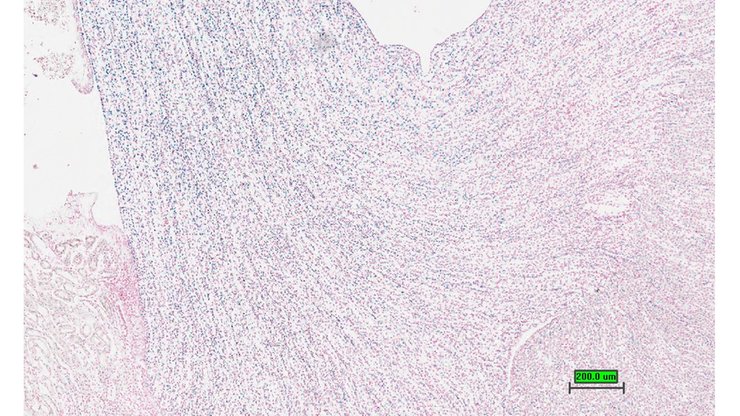

TS28: spinal cord Present UC Davis_1867069

TS28: spinal cord Present UC Davis_1867070

TS28: spinal cord Present UC Davis_1867071